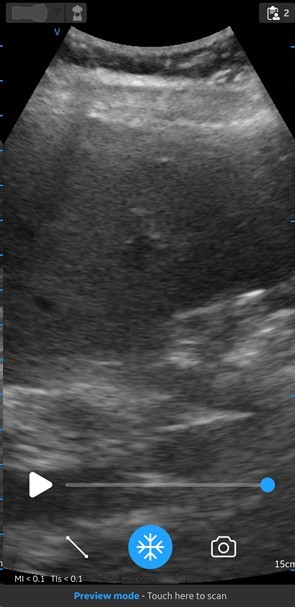

Screen with preview mode

Abdominal preset with curved